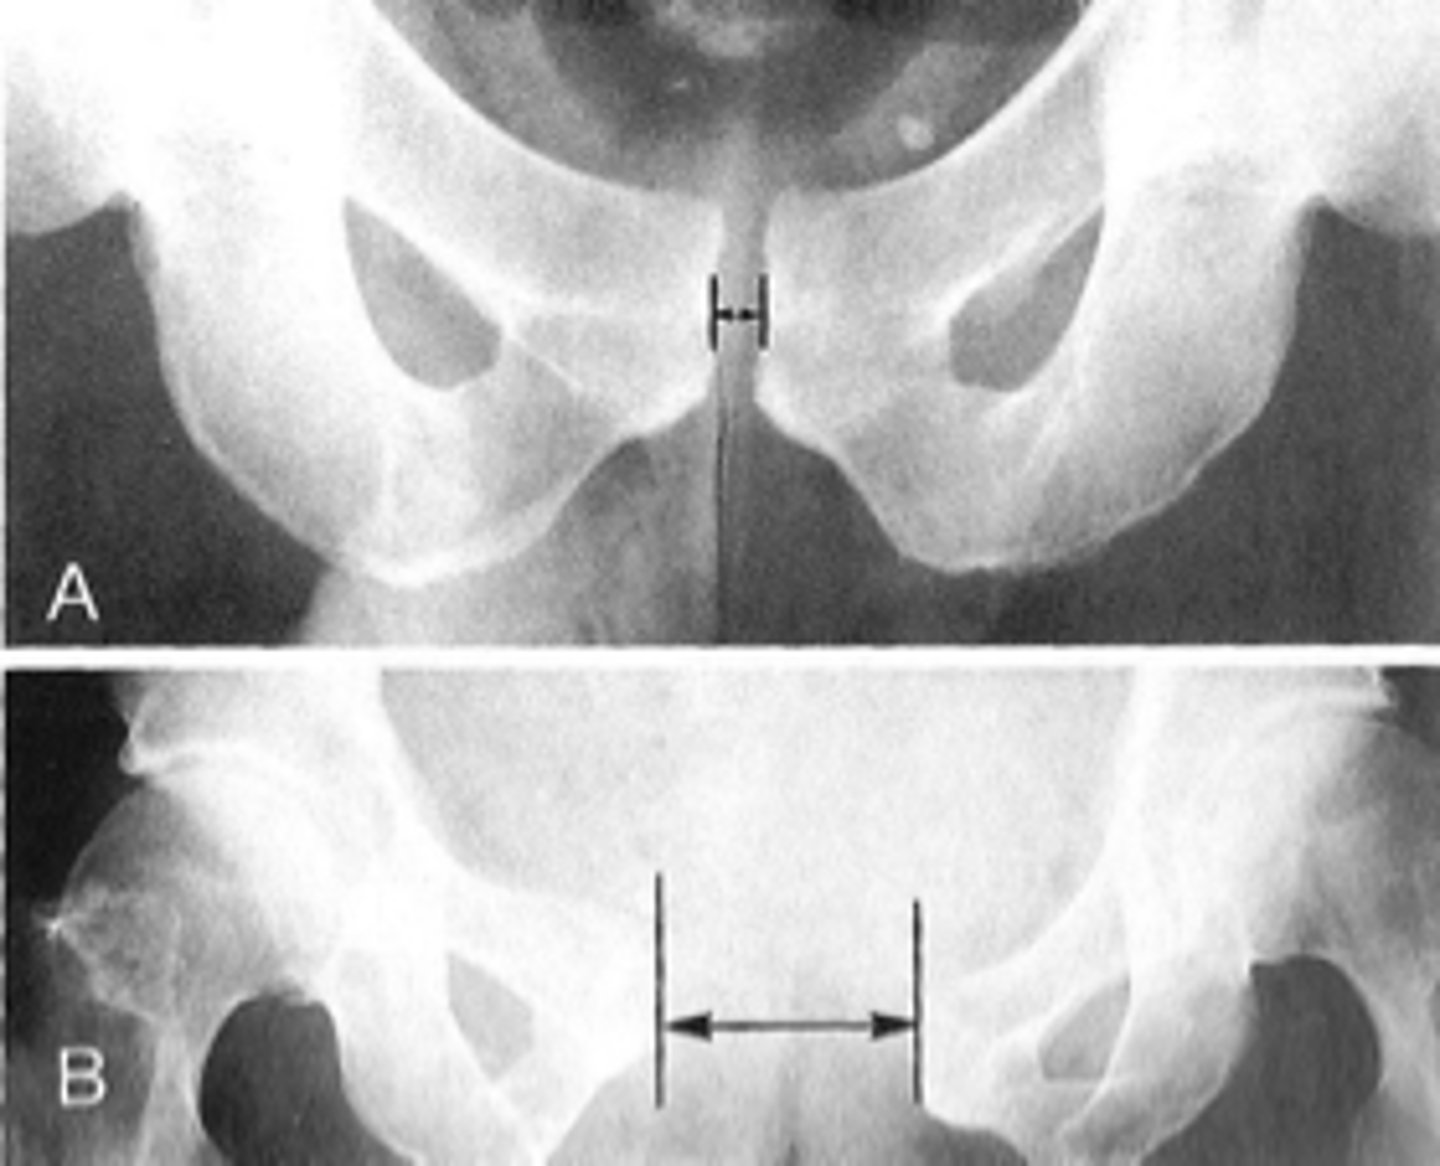

ID 2 (joint)

<p>ID 2 (joint)</p>

7

New cards

Left posterior sacroiliac joint

ID 3 (joint)

<p>ID 3 (joint)</p>